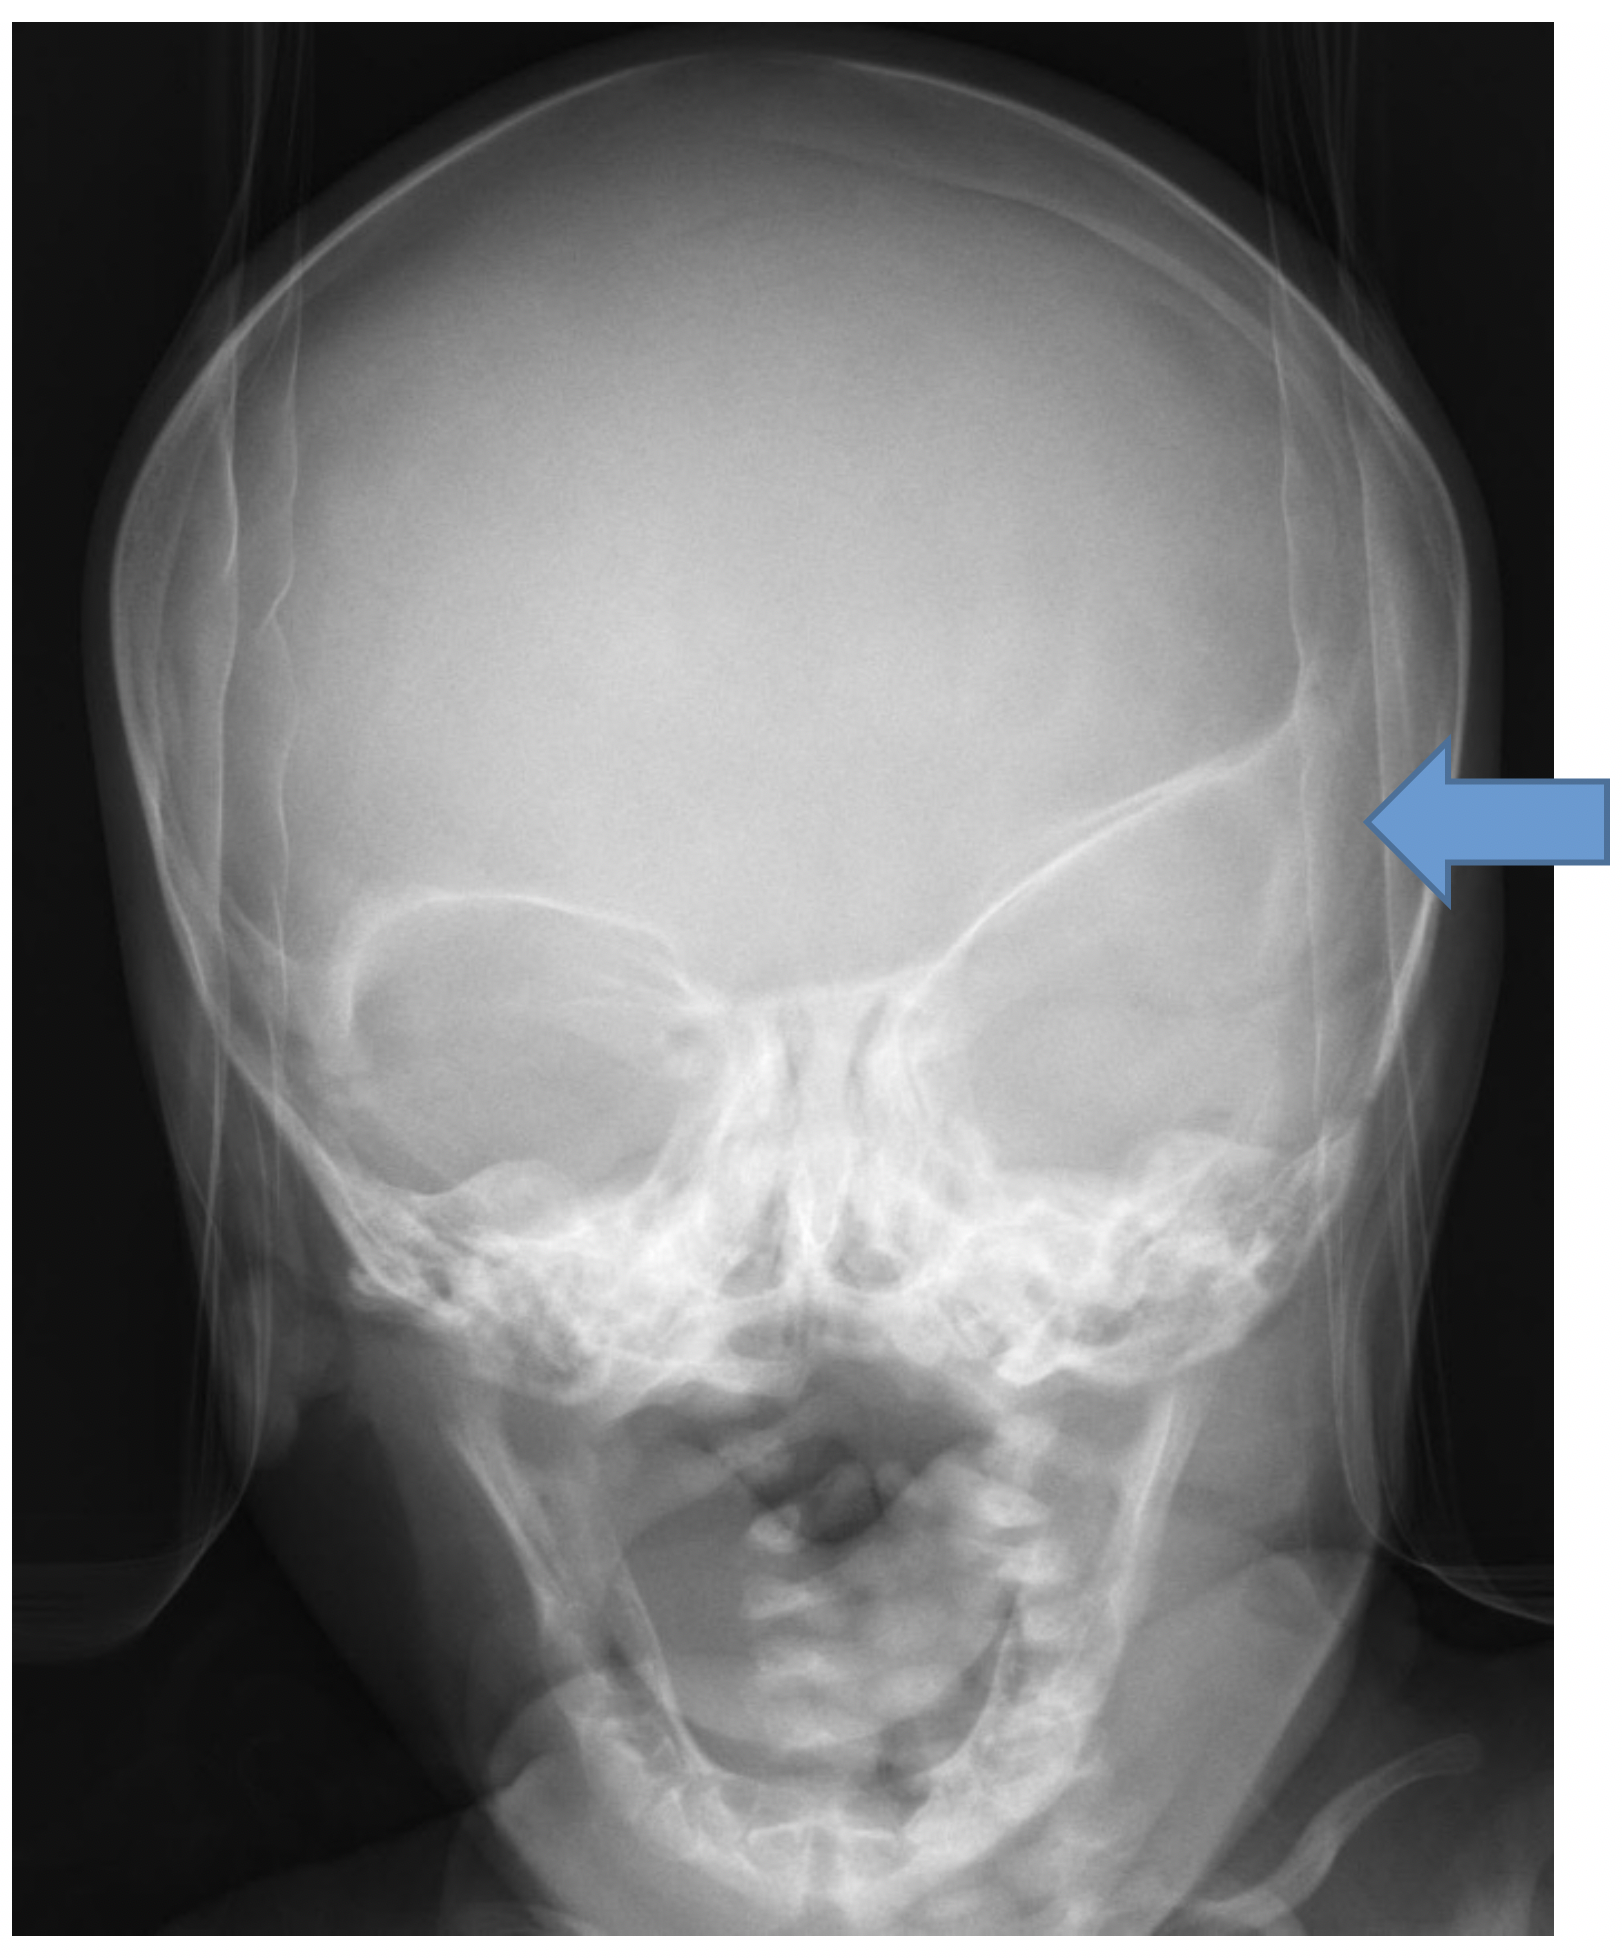

A child with unilateral coronal synostosis presents with flattening of the frontal region on the affected side, and the head shape becomes somewhat trapezoidal. On radiographs, a classic imaging finding is the “harlequin eye,” as the orbit remodels adjacent to the fused coronal suture (Fig 3).